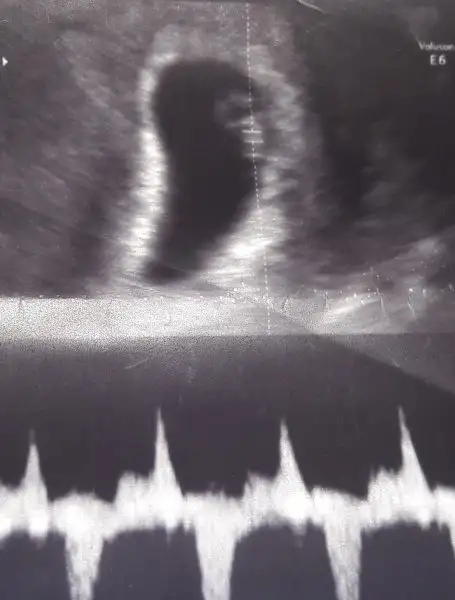

Erkek bence canım.Kizlar gunaydin bu vajinal bi onceki muayenede gozuken kesem cinsiyet tahmini alabilirmiyimEki Görüntüle 2140536

:) bende kese şeklinden dolayı dedim. Bakalım kimin dediği tutacakhadi hayırlısı inşallah ilk erkek yorumu senden geldi hallerim tipimden hep kız dediler rabbim sağlıkla dünyaya getirsin inşallah bebeklerimizi teşekkürler